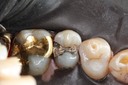

Photos of Clinical Operations

Drs. Peter Kearney, Terry McKay, John St. Germain, and Laurie Vanzella - Mentors